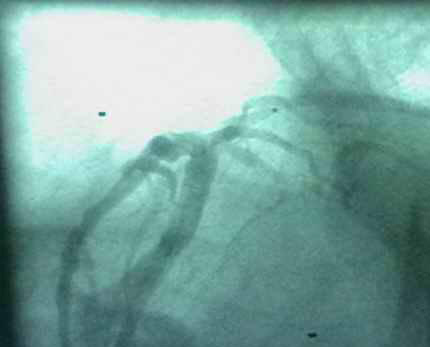

病例 3:RCA 远段CTO病变

RCA开口向上。

(RCA远端CTO)

手术步骤:AL2 GC---AL1 GC-----中等硬度导丝-----在微导管支撑下-----导丝通过病变----1.5mm 球囊预扩-----远段植入Yukon DES 2.5mm×24mm, 中段植入Yukon DES3.8mm×18mm DES (14bar, 20sec)。

进一个支架阻力并不大,但进入第二个支架时阻力很大,甚至将导引导管 (GC)弹出,(因为GC已经顶在后壁上,固定很好,第一个支架进入时GC提 供了良好的支持,纹丝不动)余老师断定:支架本身出问题,结果拉出来果然支 架远端起了毛刺(有两三根钢丝断开),只有对导管理解深的人才会做出这种判断。(我还以为他撤出支架,要预扩病变)。

· AL1-GC 支持良好,占了50%。但AL1-GC费了很大周折,靠不上去,几次进入左室,拉出,下压,使导管头上翘,旋转。当然有时借助导丝引导一下。

· 微导管(德国导管室称支持导管,support catheter)提供了良好支持. 又占了50。

· 此病例没用硬导丝就通过病变,足以说明导管支持足够好。

· 经微导管注入造影剂时,先回抽几次,有回血,说明是真腔(true lumen), 再注入造影剂。远端血管显影,说明真腔。